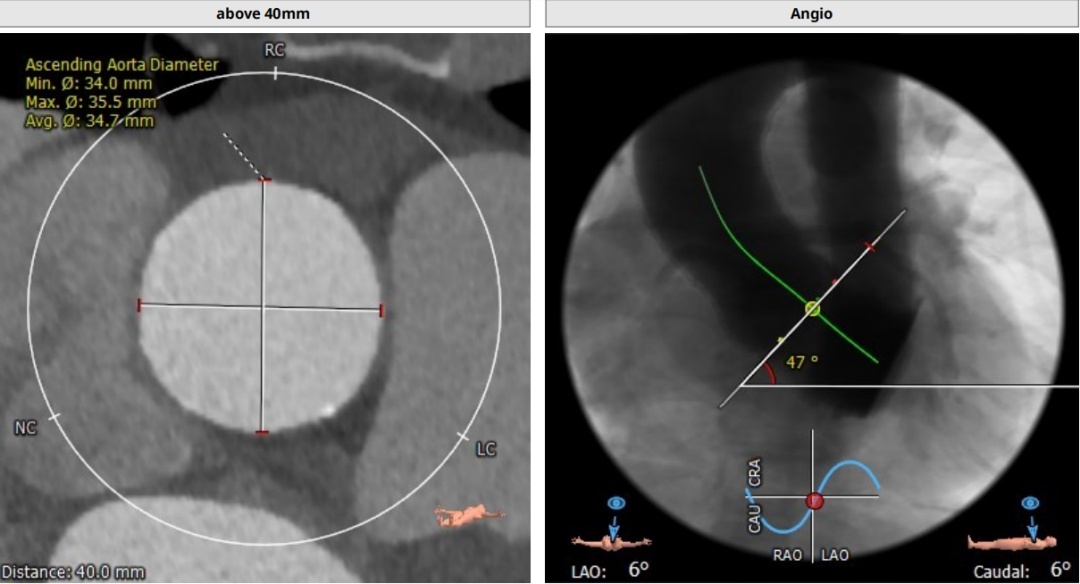

术前CT评估:

瓣环平均直径:25.2mm,左室流出道平均直径:25.5mm;

升主动脉(未见)明显扩张,心脏角度:47°;

左冠高度:12.1mm,右冠高度:16.1mm。

Annulus:25.2mm

LVOT:25.5mm

Sinus:22.1mm*32.6mm STJ:30.3mm

升主:34mm*34.7mm 主动脉成角:47°